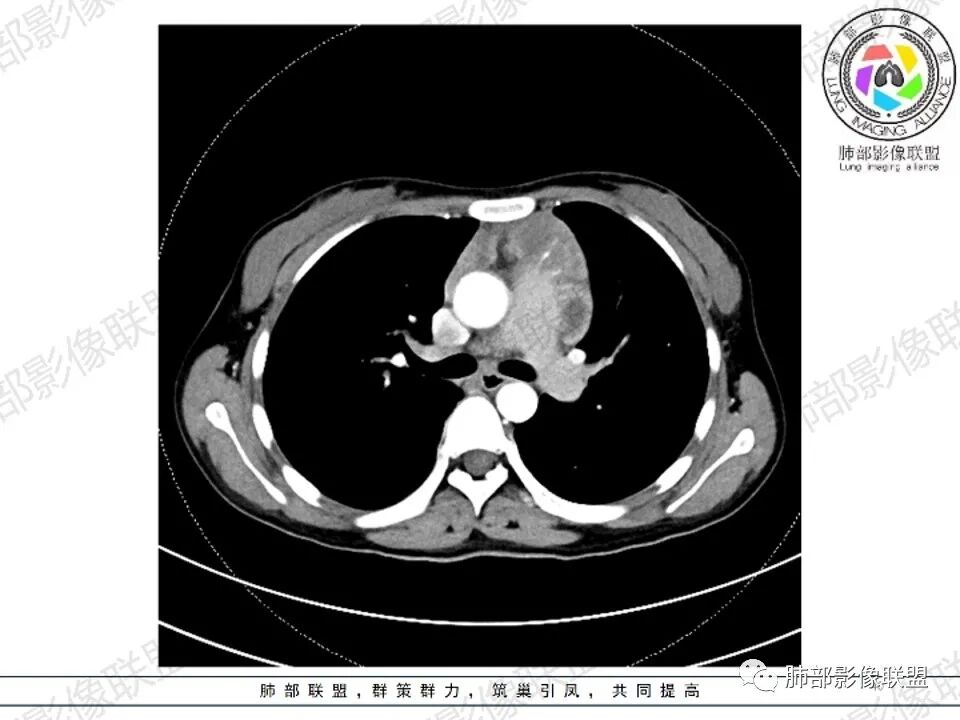

女,27,间断头晕、乏力3年,左眼视物模糊2月。贫血。胸部CT:前纵隔不规则肿块,多结节融合,边界不清,沿主动脉及肺动脉间隙生长,平扫密度欠均匀,增强扫描可见多发低密度坏死,纵隔血管供血穿行,腋窝多发大小不等淋巴结肿大。考虑恶性病变,胸腺癌?肉瘤?淋巴瘤?鉴别胸腺瘤、结节病等。

临床:年轻女性,慢性病程,多系统病变,头晕,贫血,视物模糊。

CT:定位纵膈病变,前中纵隔多发肿块,质软,塑形,密度不均匀,边界清楚。增强不均匀强化,坏死边界清楚,血管漂浮征。双侧腋下多组淋巴结肿大,明显异常强化。

考虑淋巴瘤可能。

2.影像显示前纵隔不规则块状影,依势贴附心脏大血管旁,密度不均,边界不甚清楚,有结节融合感。

3.病灶轻度不均匀强化,可见血管穿行,散在液性低密度区。

双肺门未见肿大淋巴结。

4.双侧腋窝区见增大淋巴结,边界清楚。

1.年轻女性,前纵隔不规则块状影,密度不均,边界不甚清楚,有结节融合感,轻度不均匀强化,可见血管穿行,最常见最符合的无疑是淋巴瘤!